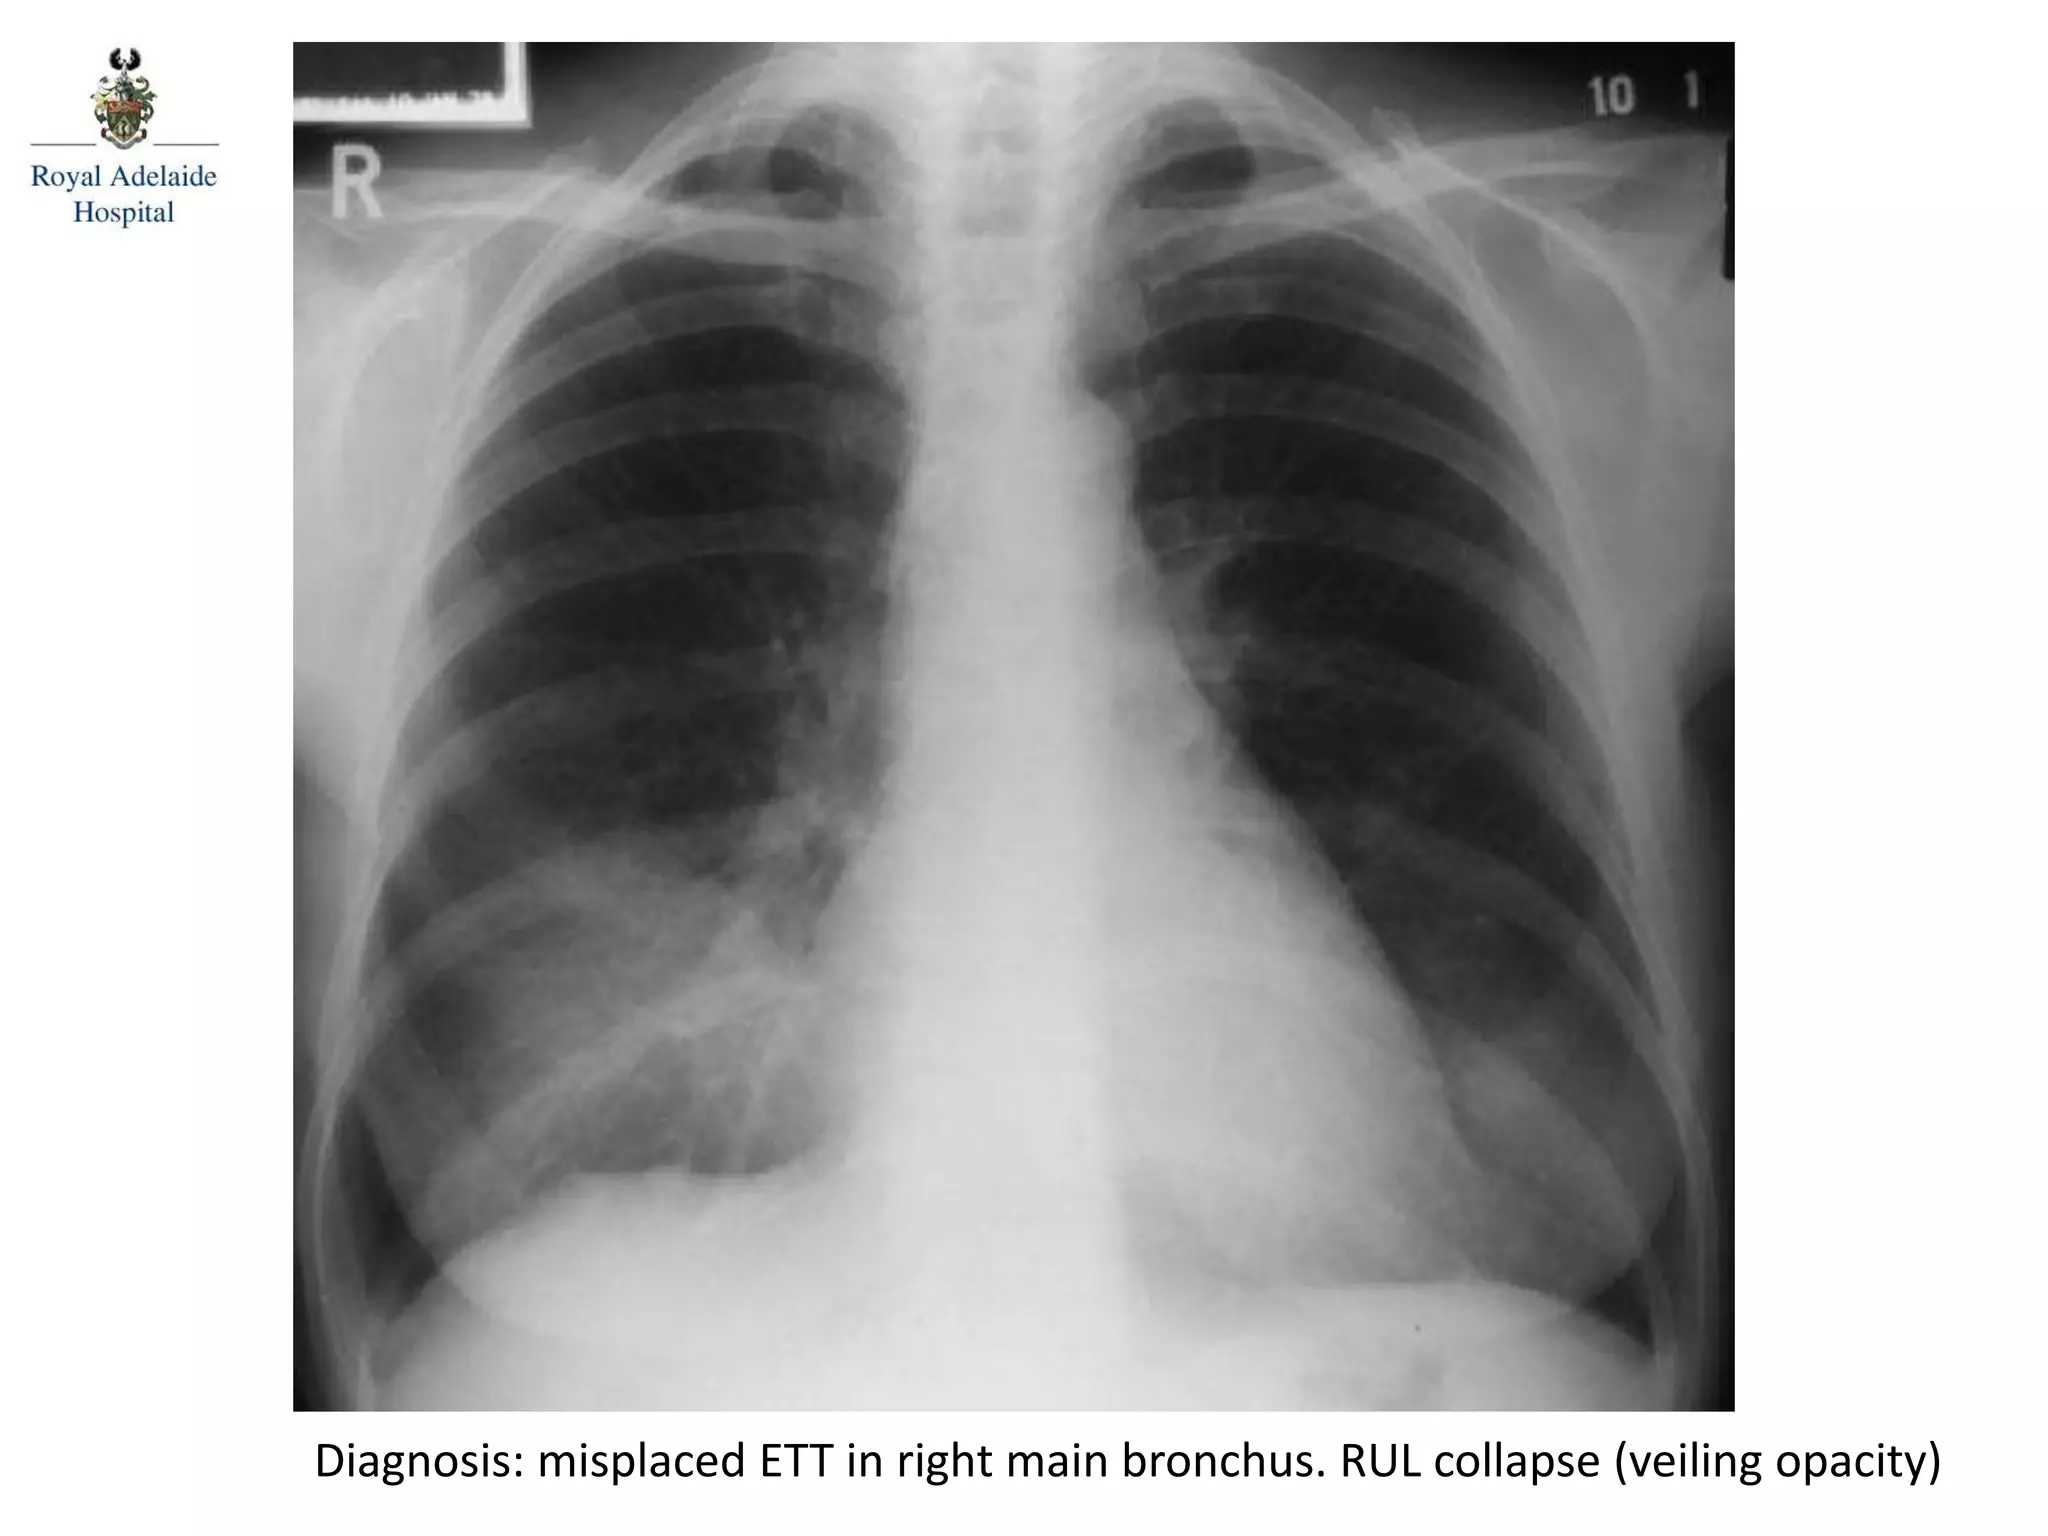

Diagnosis: misplaced ETT in right main bronchus. RUL collapse (veiling opacity)